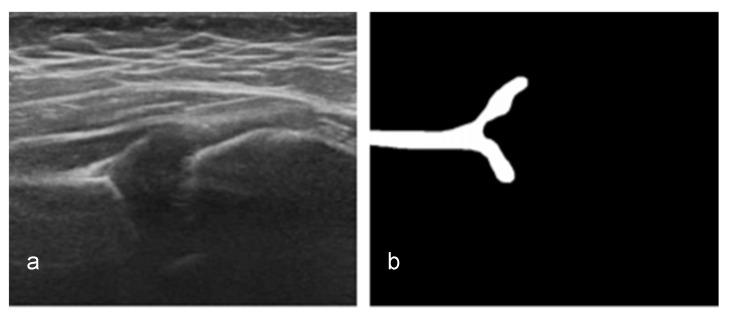

Hip joint ultrasonographic (US) imaging is the golden standard for developmental dysplasia of the hip (DDH) screening. However, the effectiveness of this technique is subject to interoperator and intraobserver variability. Thus, a multi-detection deep learning artificial intelligence (AI)-based computer-aided diagnosis (CAD) system was developed and evaluated. The deep learning model used a two-stage training process to segment the four key anatomical structures and extract their respective key points. In addition, the check angle of the ilium body balancing level was set to evaluate the system's cognitive ability. Hence, only images with visible key anatomical points and a check angle within ±5° were used in the analysis. Of the original 921 images, 320 (34.7%) were deemed appropriate for screening by both the system and human observer. Moderate agreement (80.9%) was seen in the check angles of the appropriate group (Cohen's κ = 0.525). Similarly, there was excellent agreement in the intraclass correlation coefficient (ICC) value between the measurers of the alpha angle (ICC = 0.764) and a good agreement in beta angle (ICC = 0.743). The developed system performed similarly to experienced medical experts; thus, it could further aid the effectiveness and speed of DDH diagnosis.

髋关节超声(US)成像术是发育性髋关节发育不良(DDH)筛查的金标准。然而,该技术的有效性受到操作者间和观察者内变异性的影响。因此,开发并评估了一种基于多检测深度学习人工智能(AI)的计算机辅助诊断(CAD)系统。深度学习模型采用两阶段训练过程来分割四个关键解剖结构并提取其各自的关键点。此外,设置了髂骨体平衡水平的检查角度以评估该系统的认知能力。因此,分析中仅使用具有可见关键解剖点且检查角度在±5°以内的图像。在原始的921张图像中,有320张(34.7%)被系统和人类观察者均认为适合筛查。在合适组的检查角度方面观察到中度一致性(80.9%)(Cohen's κ = 0.525)。同样,在α角测量者之间的组内相关系数(ICC)值方面存在高度一致性(ICC = 0.764),在β角方面存在良好一致性(ICC = 0.743)。所开发的系统表现与经验丰富的医学专家相似;因此,它可以进一步提高DDH诊断的有效性和速度。